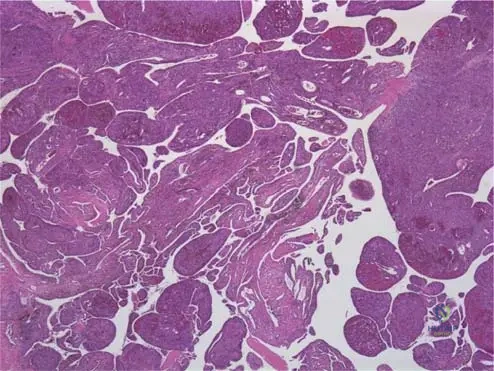

A synovial biopsy is obtained from a 39-year-old patient with chronic knee effusions and periarticular erosions.

View Answer & Explanation

Correct Answer: C

Rationale: The text explicitly states, "Lipidor hemosiderin-filled macrophages are present" in the microscopic examination of PVNS. Fig. 10.7 shows the villous masses, which microscopically contain these cells. Main Distractor: A) Lymphocytes and plasma cells. While some inflammatory cells may be present, the defining characteristic of PVNS microscopically is the presence of lipid- and hemosiderin-filled macrophages, not primarily lymphocytes and plasma cells, which are more indicative of chronic inflammatory arthritides.